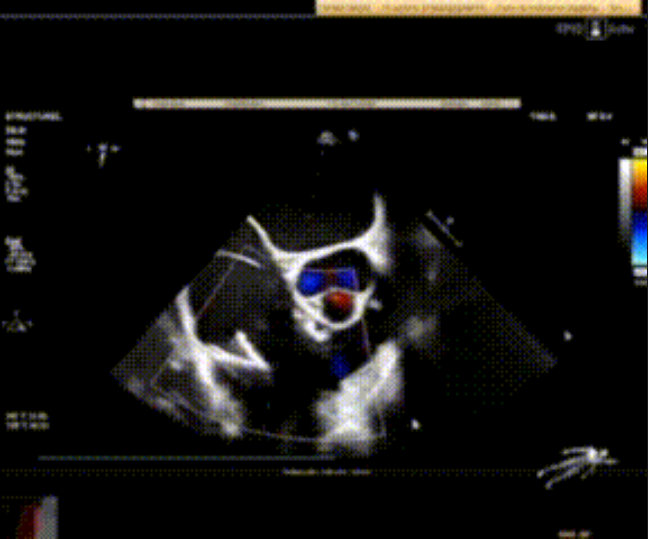

術(shù)前心臟超聲提示:極重度三尖瓣返流,右房容積明顯增大,三尖瓣瓣環(huán)顯著擴(kuò)張。

術(shù)后心臟超聲提示:LuX-Valve Plus植入后,三尖瓣瓣環(huán)處可見(jiàn)人工瓣膜回聲,未見(jiàn)返流,人工瓣膜穩(wěn)定,瓣葉開(kāi)閉良好,連續(xù)多普勒估測(cè)三尖瓣平均跨瓣壓差僅為1mmHg。